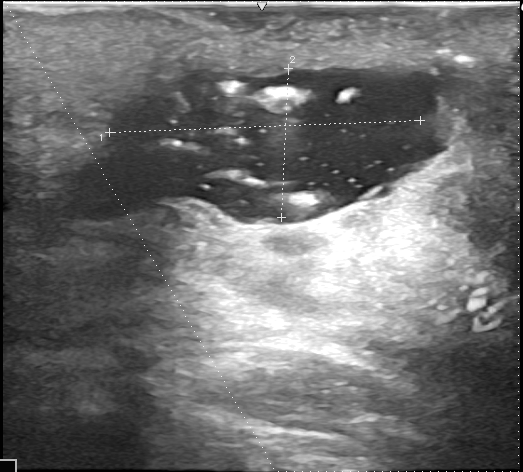

診察時、後頚部に直径80mmの発赤を伴うしこりがあり、超音波検査により典型的な感染性粉瘤と診断されました。一部、僧帽筋筋膜にも炎症が波及していました。採血で糖尿病も認められたため、糖尿病の治療と並行して粉瘤の治療を行う方針となりました。

初回手術術前